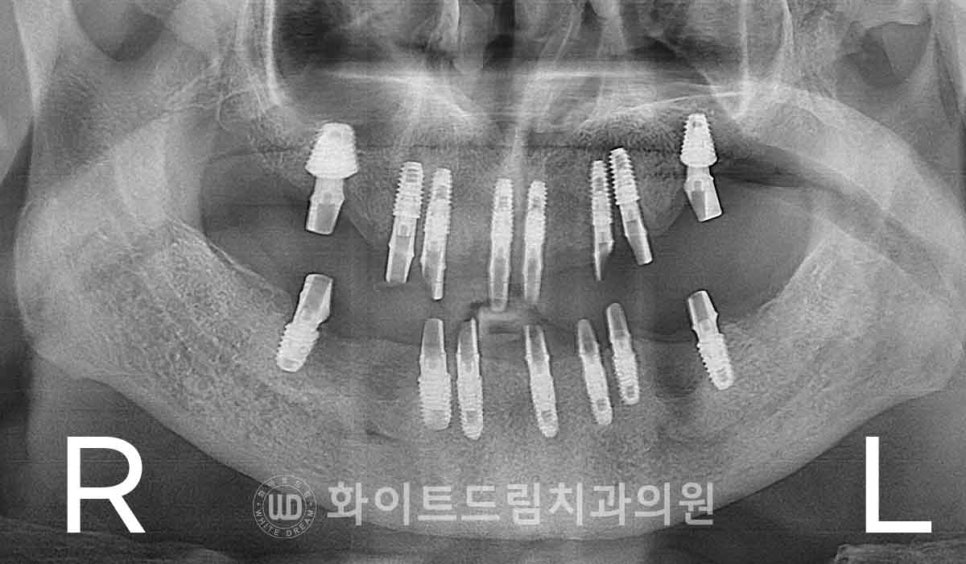

상악 → 하악 순으로 총 2번에 걸쳐 전체 임플란트를 식립하였습니다.

상악 발치 & 임플란트 수술, 서울전체임플란트잘하는치과 : 24.02.15

하악 발치 & 임플란트 수술, 서울전체임플란트잘하는치과 : 24.02.22

염증으로 인해 골 소실이 심했던 부위는 피하고,

상대적으로 잇몸뼈가 남아 있는 부위로 임플란트를 식립하였습니다.

이렇게 하면 임플란트의 초기 고정력을 안정적으로 확보할 수 있을 뿐만 아니라,

불필요한 뼈이식을 줄여 환자분의 부담을 덜 수 있는 장점도 있습니다.

또한 수술 부위의 회복이 원활해져 전체 치료 기간을 단축할 수 있다는

장점도 가지고 있죠. ^^

약 4~5개월간의 임플란트와 잇몸뼈 회복 기간을 거치면

식립된 임플란트가 잇몸뼈와 단단히 결합되어

부드러운 음식을 섭취할 수 있을 정도의 고정력을 얻게 됩니다.